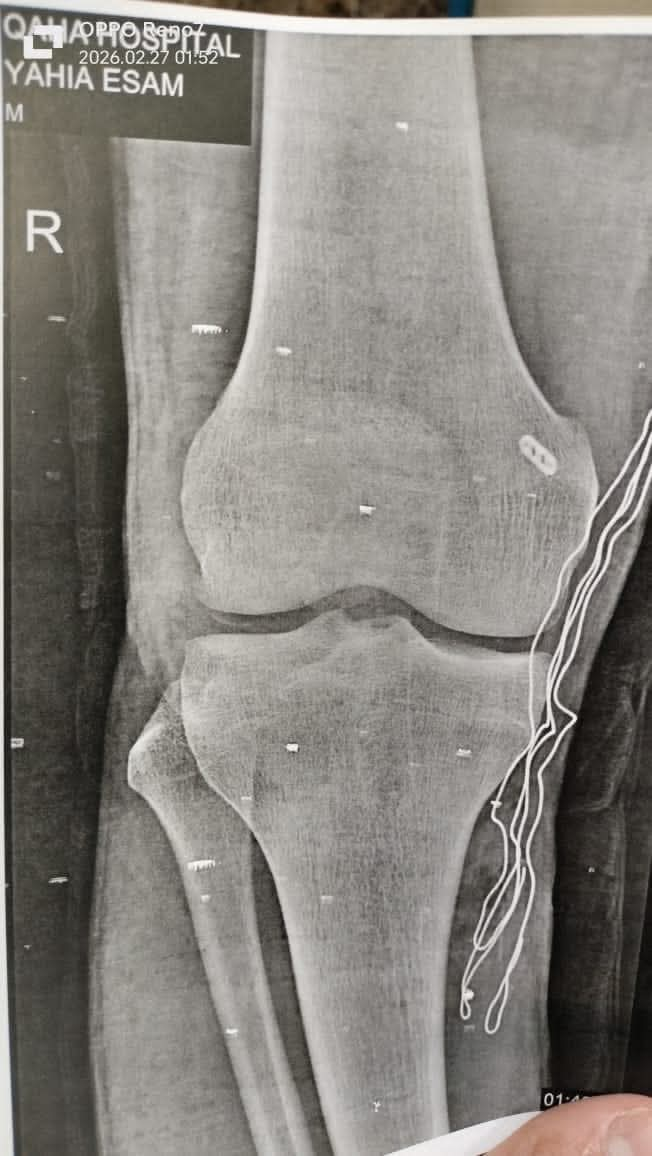

قطع بالرباط الصليبي الخلفي

المستشفى استقبل المريض وهو يشكو من آلام شديدة وعدم استقرار بمفصل الركبة. وعلى الفور، تم إجراء الفحص الإكلينيكي اللازم، وعمل أشعة الرنين المغناطيسي، التي كشفت وجود قطع بالرباط الصليبي الخلفي، وهي من الإصابات غير الشائعة مقارنة بإصابات الرباط الصليبي الأمامي المنتشرة بين الرياضيين.

وعقب التشخيص الدقيق، قرر الفريق الطبي التدخل الجراحي العاجل، حيث تم إجراء إعادة بناء الرباط الصليبي الخلفي بالمنظار باستخدام رقعة وترية، مع تثبيتها بواسطة “زرار طبي” ومسمار ذاتي الامتصاص، وفق أحدث المعايير الطبية المعتمدة في هذا النوع من الجراحات الدقيقة، وقد تكللت العملية بالنجاح واستقرت حالة المريض.